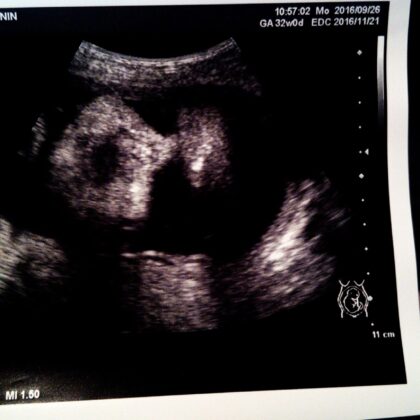

32w検診。

今日はエコーで赤ちゃんの顔がよく見えました♡

いつもはこっちを向いていなくて、あまりお顔が見えなかったのですが、今日はめっちゃこっち向いてた!!

なんだか長男に似てる気がする〜♡

出産や産後のこと、少し不安になっていましたが、可愛いお顔が見れて嬉しかったな。